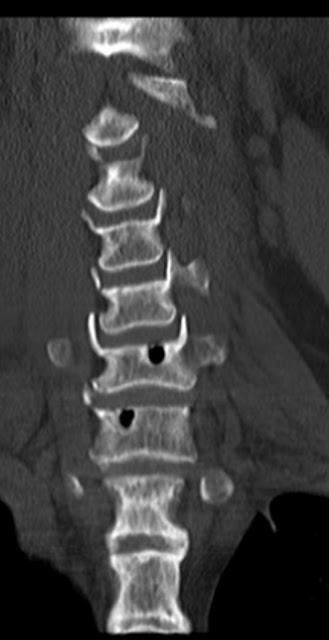

Явление вакуума в межпозвонковых дисках

Случай 2: Внутрикостная пневмоцистика

Внутрикостная пневмоцистика